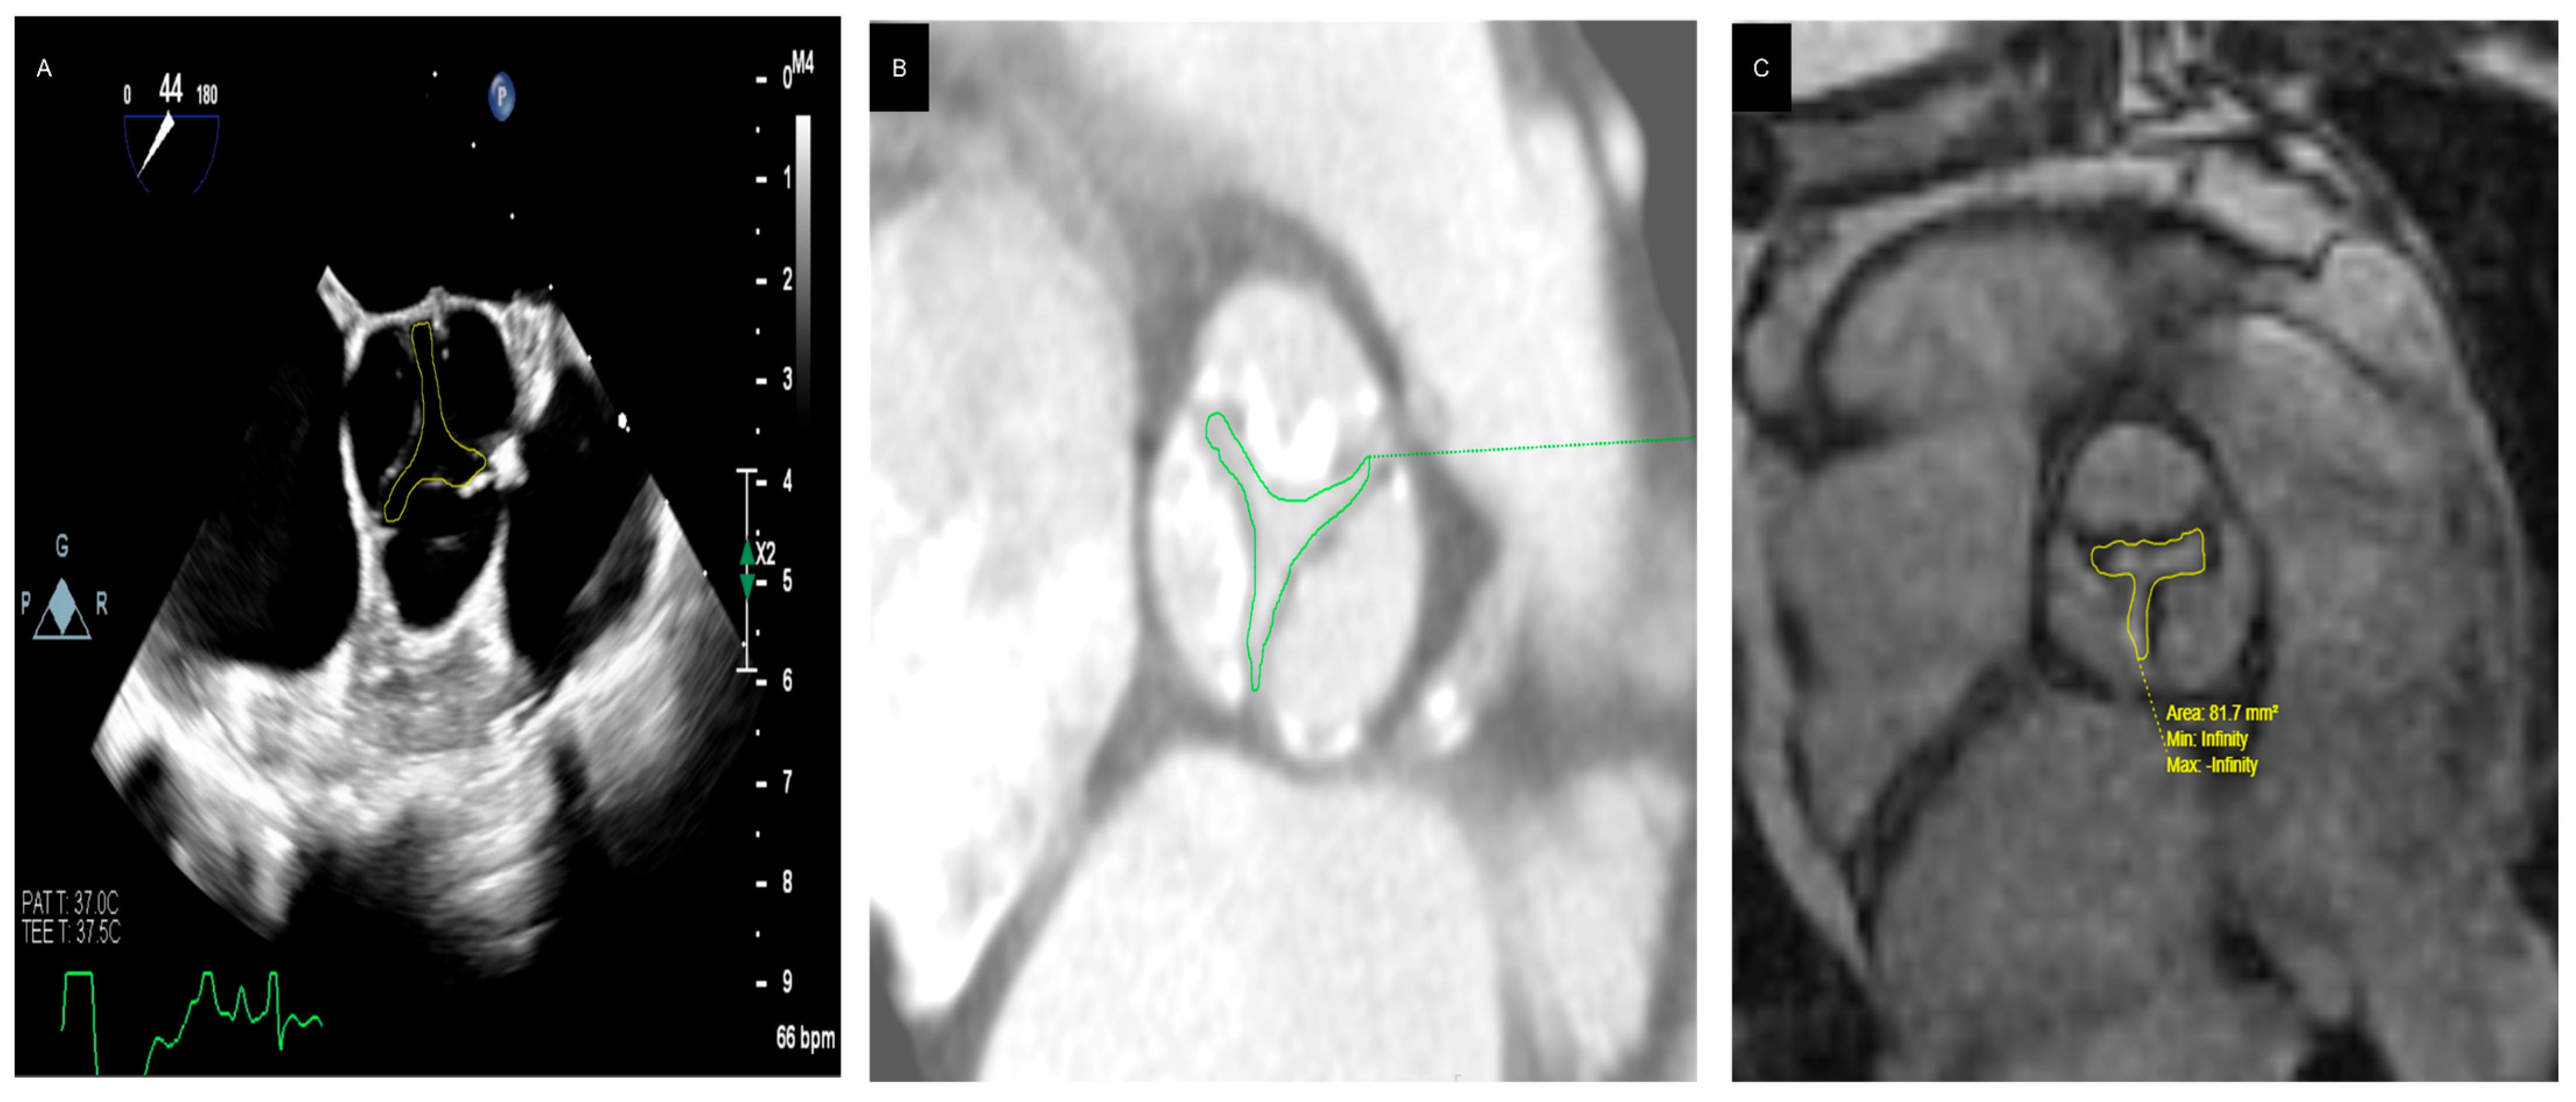

Figure 3. (A) 73 year old male patient with discordant high gradient aortic stenosis. Left ventricle outflow tract diameter = 2.52 cm (A). (B) shows a parasternal short axis view of the aortic valve with severe calcification. Aortic Valve VTI is 110.18 cm, the mean gradient is 53.64 mmHg (C), and LVOT VTI is 27.88 cm (D). As a result, the aortic valve area by VTI is 1.26 cm2, cardiac output is 8.06 L/min, and cardiac index is 4.41 L/min/m2.